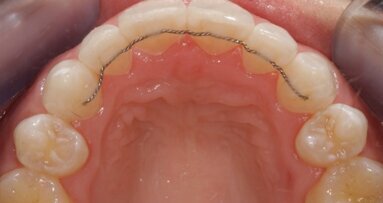

After four months, the alignment of the lower teeth was complete and impressions were taken for a fixed bonded retainer―a multi-strand stainless-steel retainer bonded to the palatal surface of the front six teeth with the aid of a custom placement jig. Owing to the type of occlusion, the patient continues to wear an Essix-type retainer on the upper teeth.